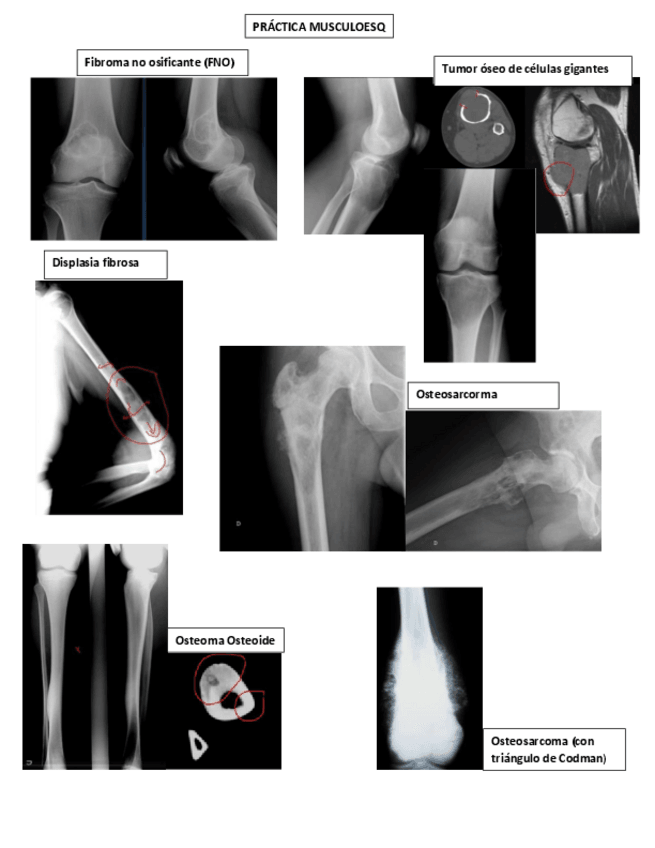

He publicado nuevos practicas de 2º Radiologia General: Practicas-Radiologia.-MSK.pdf

Practica-musculoesqueletico.pdf

Practicas-Aparato-Locomotor.pdf

PRACTICA-LOCOMOTOR.pdf